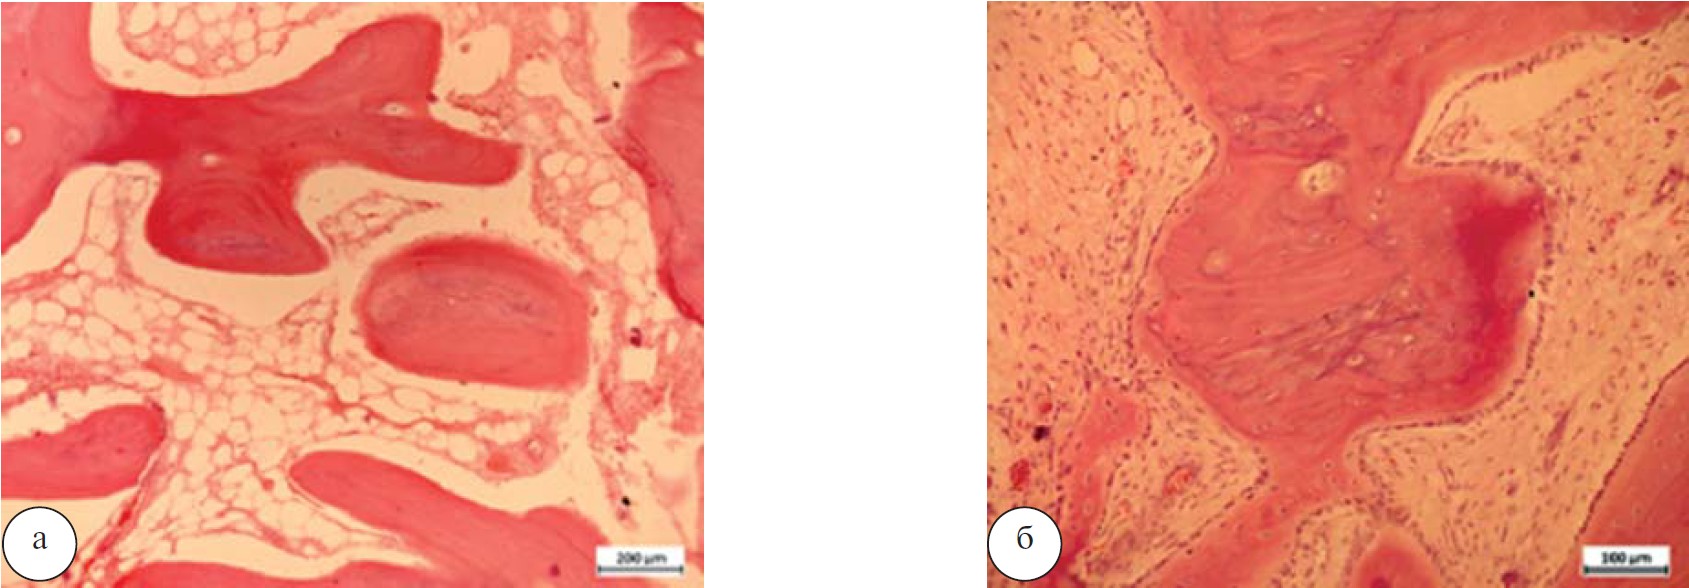

При изучении гистологических препаратов головки бедренной кости больных хроническим остеомиелитом в периоде обострения, с преобладанием картины гнойного воспаления определялась рарефицированная губчатая кость головки бедра с почти полным разрушением суставного хряща, истончением субхондральной костной пластинки, некрозом костных трабекул, замещением межтрабекулярного пространства полями некротизированного детрита, скоплениями гнойного экссудата, грануляционной тканью и полями фиброзирования (рис. 2).

Рис. 2. Обзор участков головки кости. Суставной хрящ головки отсутствует. Окраска гематоксилином и эозином.

Ув. х31,25 (а). Очаги скопления кокковой микрофлоры в массах детрита. Ув. х500 (б).

В некоторых участках головки бедренной кости межтрабекулярные пространства были заполнены гнойным экссудатом, обнаруживались поля грануляционной ткани разной степени зрелости (рис. 3).

Рис. 3. Фрагмент головки бедренной кости. Межтрабекулярные пространства в головке бедра заполнены гнойным экссудатом: а — зрелая, с начальными признаками фиброзировния, ув. х 125; б — грануляционная ткань в межтрабекулярных пространствах губч атой некротизированной кости, ув. х250. Окраска гематоксилином и эозином.

По данным гистологического исследования выявлено наличие гранулематозного компонента с формированием мелких рыхлых безказеозных гранулем лимфоцитарного и макрофагального состава с наличием гигантских многоядерных клеток типа инородных тел. Определялись участки репаративного костеобразования на поверхности частично некротизированных костных трабекул со слоем новообразованного остеоида и слоем остеобластов на эндостальной поверхности костного трабекулярного комплекса. В межтрабекулярном пространстве - грануляционная ткань с участками фиброретикулярной перестройки (рис. 7).

Рис. 7. Хронический остеомиелит. Остеонекроз: а — запустевшие лакуны остеоцитов, отсутствие слоя остеобластов на поверхностях рарефицированных костных трабекул. В межтрабекулярных пространствах хлопьевидный аморфный детрит и жировые капли. Ув. х 125; б — участок репаративного остеогенеза при хроническом остеомиелите, напластование остеоида на поверхности предсуществовавшей, частично некротизированной трабекулы. Окраска гематоксилином и эозином. Ув. х250.